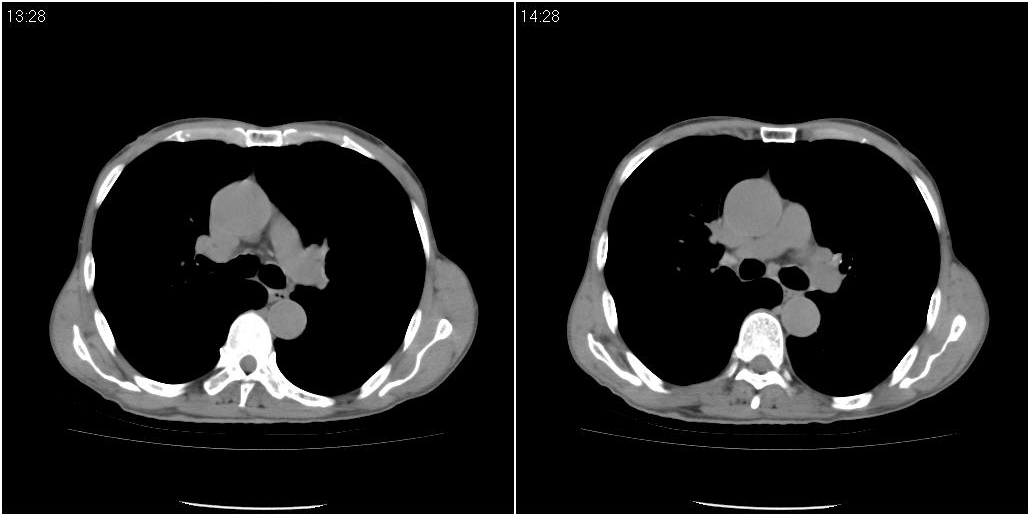

右肺中叶阻塞性不张及肺炎,高度怀疑支气管占位,建议纤支镜检查!

右中肺阻塞性炎症,建议纤支镜!双下支扩感染。

1)右肺中叶慢性炎症并支气管扩张,节段性肺不张。2)两肺下叶支气管扩张。

1)右肺中叶慢性炎症并支气管扩张,节段性肺不张。2)左肺下叶支气管扩张